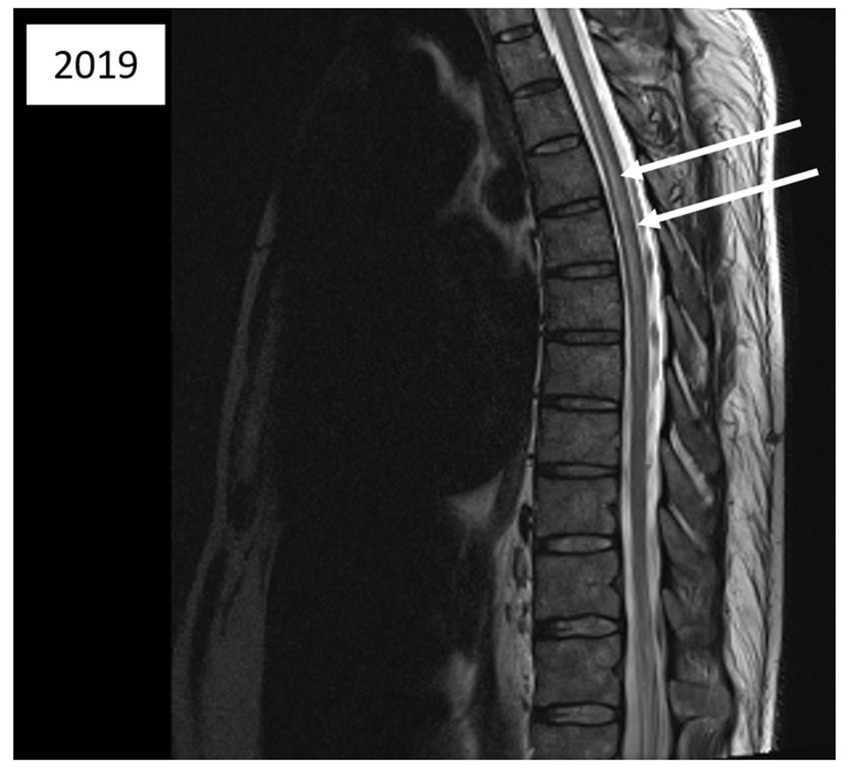

Figure 3

Magnetic resonance imaging of the thoracic spinal cord; sagittal T2-weighted images acquired 5 days after the second diving incident reveal abnormalities in spinal cord signal intensity (indicated by arrows).

Five days after the second incident, a medullary MRI was performed, which revealed a T2-weighted hypersignal extending intramedullary from level T2 to T8 in sagittal sections (see Figure 3). This hypersignal affected both the posterior cords and the gray matter in the axial section (Figure 4).

Another aspect for discussion pertains to the region of spinal cord injury identified during the MRI conducted after the second incident. Literature data from several years ago (7, 9) indicate that MRI findings in cases of Spinal cord DCS more commonly reveal ischemic lesions in the posterior or lateral columns of the spinal white matter, with central gray matter involvement being less prevalent. Nevertheless, gray matter involvement can also manifest in certain severe cases of Spinal cord DCS (15), as observed in the case we present (Figures 3, 4). We attribute this observation to advancements in imaging techniques with newer generations of MRI, facilitating a more precise analysis of spinal cord lesions, including the more frequent detection of gray matter involvement in Spinal cord DCS cases compared to previous methodologies.